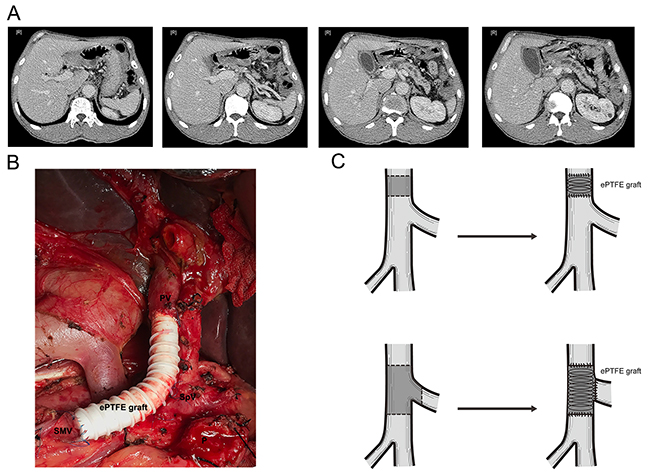

For patients with resectable tumors, PD with PVR was performed. PD was performed a classic Whipple procedures. The Whipple’s procedure commonly performed was PD with end-to-side pancreaticojejunostomy, end-to-side hepaticojejunostomy, and anterior-colic gastrojejunostomy. Two drains were placed at the end of the procedure in the foramen of Winslow and along with upper and below edge of the pancreaticojejunostomy. PVR were carried out en-bloc as primary closure of the vein, and reconstructed with ePTFE vascular grafts (Bard Peipheral Vascular, Inc).

For patients with unresectable tumors, SB (hepaticojejunostomy with or without gastrojejunostomy) was performed. Intraoperative FNA was also conducted to provide the pathological evidence of the diagnosis of PDAC (Schema of surgical procedures were shown as Figure 4).

Figure 4: Schema of surgical procedures. (A) CT scan of PDAC patients with PV involvement. (B) Surgical procedure of PD combined with PVR. (C) Sketch map of PD combined with PVR. Abbreviation: CT= Computer tomography, PD= pancreaticoduodenectomy, PDAC= pancreatic ductal adenocarcinoma, PV= Portal vein, PVR=Portal vein resection.